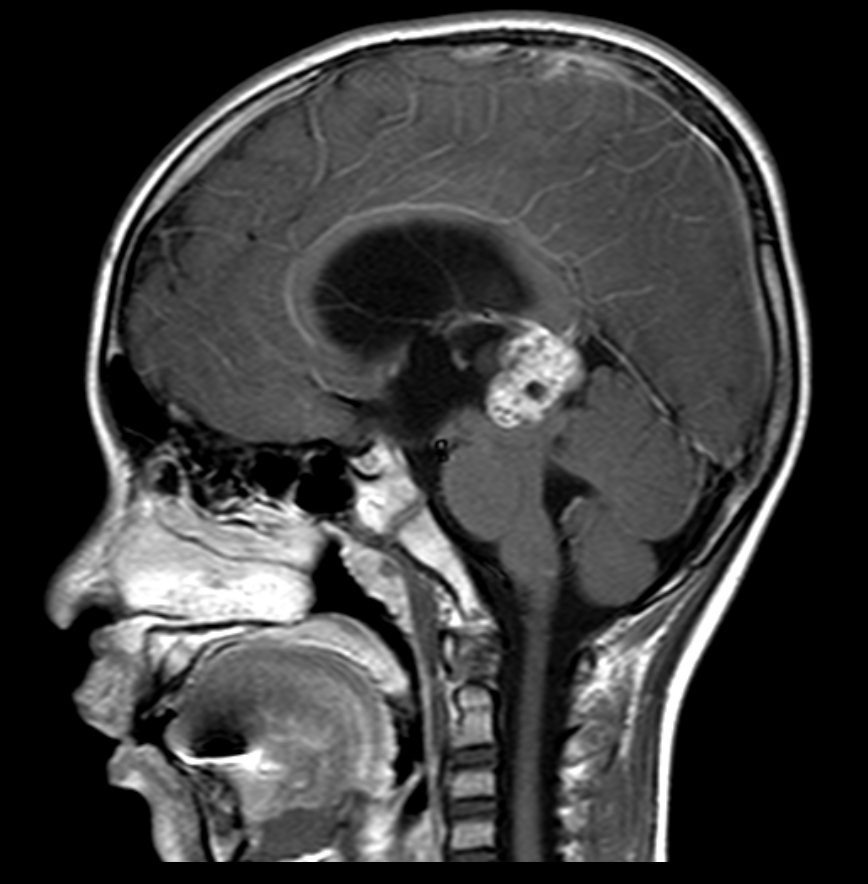

松果体肿瘤 是一种少见的脑肿瘤,它们从松果体或松果体周围的组织开始。松果体位于大脑的中央,就在脑干后面,它产生控制睡眠的褪黑激素。松果体肿...

松果体是位于大脑底部后部、脑干顶部附近的一个小器官。它负责产生几种激素,包括调节睡眠-觉醒周期和一些生殖功能的褪黑激素。松果体区域的肿瘤很...

松果体区肿瘤 是一种始于大脑中心的松果体内或周围的脑肿瘤。松果体肿瘤通常不会扩散到身体的其他部位。但它们可能会因继续生长并压迫周围组织而引...

松果体肿瘤手术难度大吗?松果体位于大脑重要位置,其之于人体的重要性可想而知。松果体区又称三脑室后部〞,松果体上方为胼胝体压部,正前方为三...

松果体区肿瘤的位置深在、周围解剖结构复杂,且毗邻重要的血管神经结构,故而手术切除困难,风险较高,该区域手术死亡率曾高达50%~70%。随...